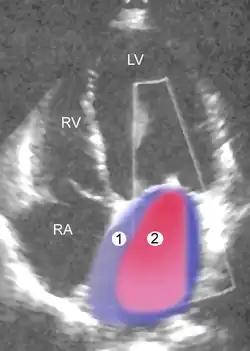

|

| Schwere MI | Legende |

| 1 Linker Vorhof (LA) – 2 MI-Jet LV Linke Herzkammer – RV Rechte Herzkammer – RA Rechter Vorhof | |

Die Farbdoppler-Echokardiografie (s. Abb.) zeigt eine vorhandene Mitralinsuffizienz als (meist blau dargestellte) Farbwolke im linken Vorhof, die als Insuffizienzjet oder Regurgitationsjet bezeichnet wird. Breite und Ausdehnung dieser Farbwolke erlauben bereits eine grobe Abschätzung des Schweregrades der Insuffizienz. Darüber hinaus können meist bei der Echokardiografie bereits der zugrundeliegende Mechanismus (Ringdilatation, inkompletter Klappenschluss, Endokarditis, Prolaps, flail leaflet, „unklar“) und die Lokalisation eventueller Klappenveränderungen dokumentiert werden.[20]